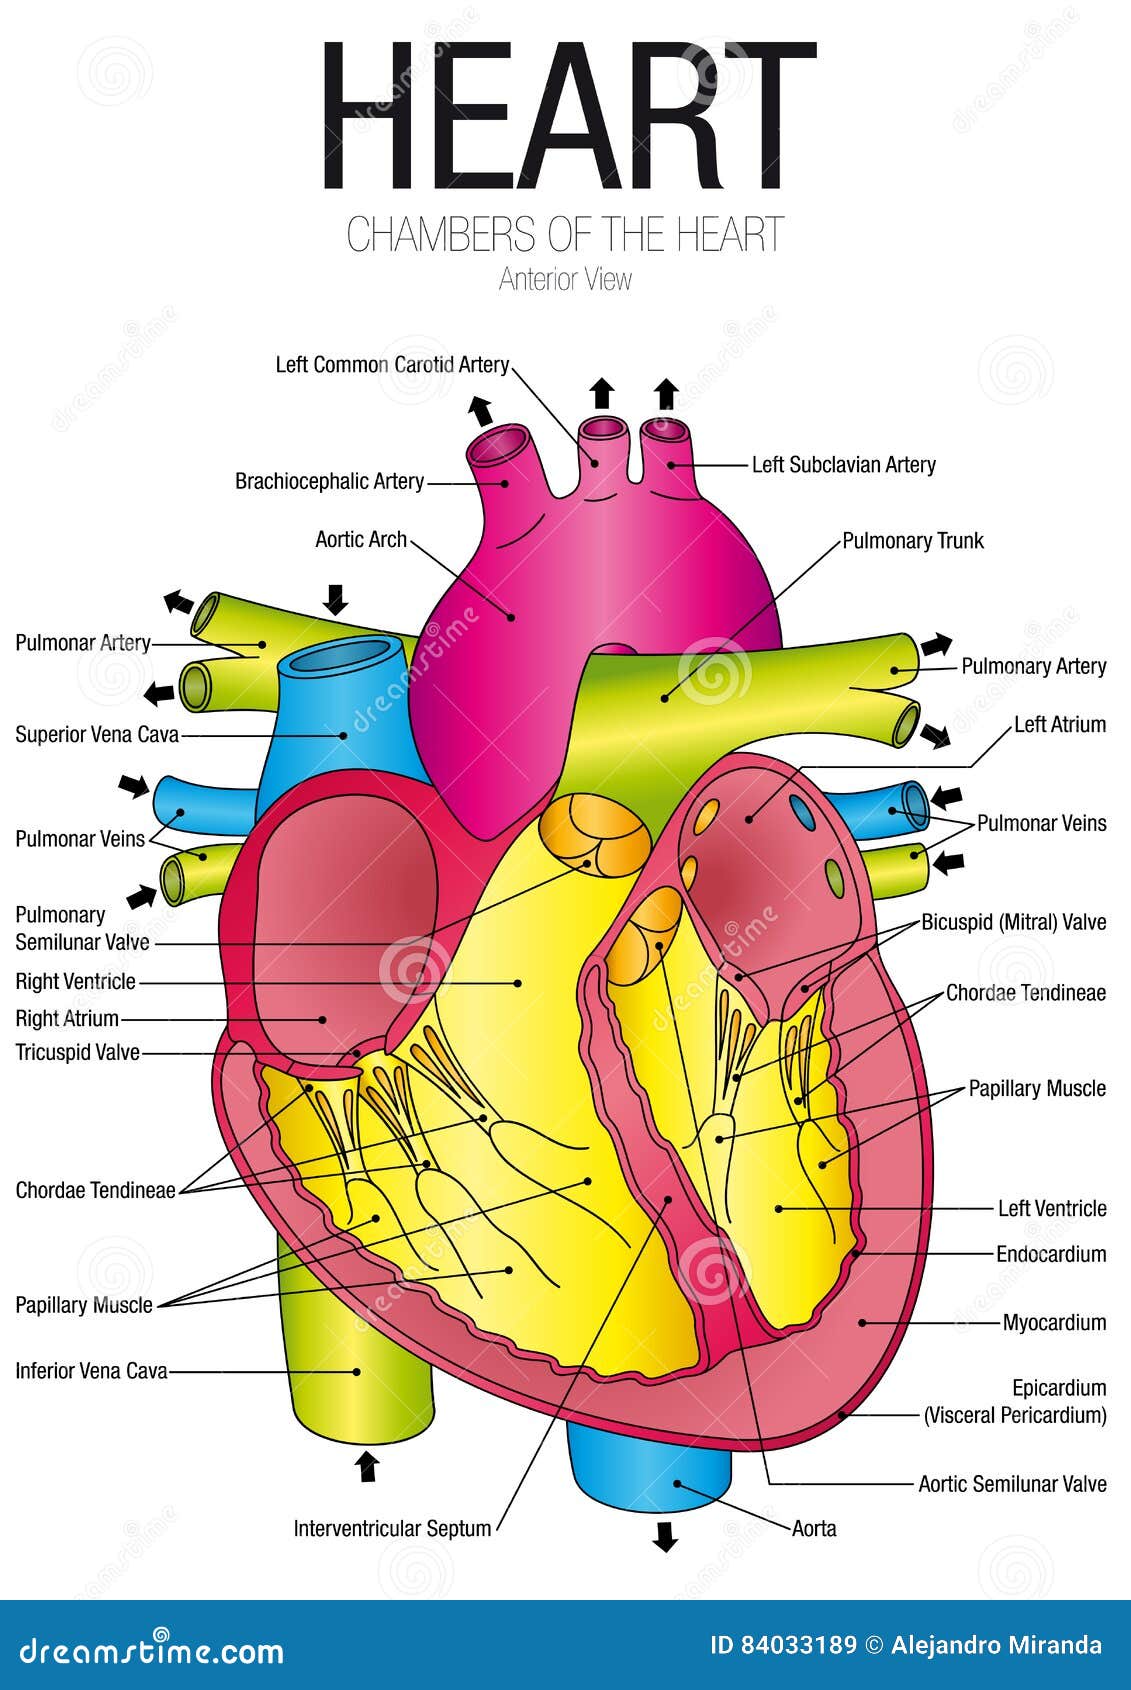

37+ black and white diagram of the heart

Anterior Heart Diagram Stock Illustrations 34 Anterior Heart Diagram Stock Illustrations Vectors Clipart Dreamstime

Heart Parts Labeled

Human Heart Black And White Stock Photos Images Alamy